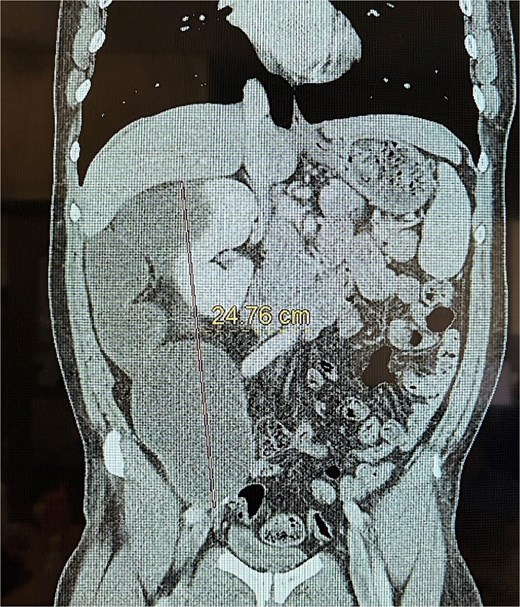

This is a 53-year-old male with no notable past medical history who presented with a 6-week history of persistent right-sided flank pain. Notably, the patient denied systemic symptoms such as weight loss, nausea, vomiting, or constipation and he denied any urinary symptoms, including dysuria or hematuria. Initial evaluation in the emergency department (ED) included a computed tomography (CT) scan of the abdomen and pelvis, which revealed a 23 cm cystic retroperitoneal mass displacing the right kidney as seen in Figs 1 and 2. The patient was discharged from the ED with a recommendation for follow-up with a surgical specialist.

Upon further evaluation by the surgeon at follow-up, a repeat CT scan was obtained and demonstrated that the mass had grown to 28.5 cm and displayed a lobulated cystic structure with calcifications at its inferior margin. The mass was abutting the cecum and was suspected to be a mucinous neoplasm. Given the concerning size and characteristics of the tumor, surgical resection was recommended.